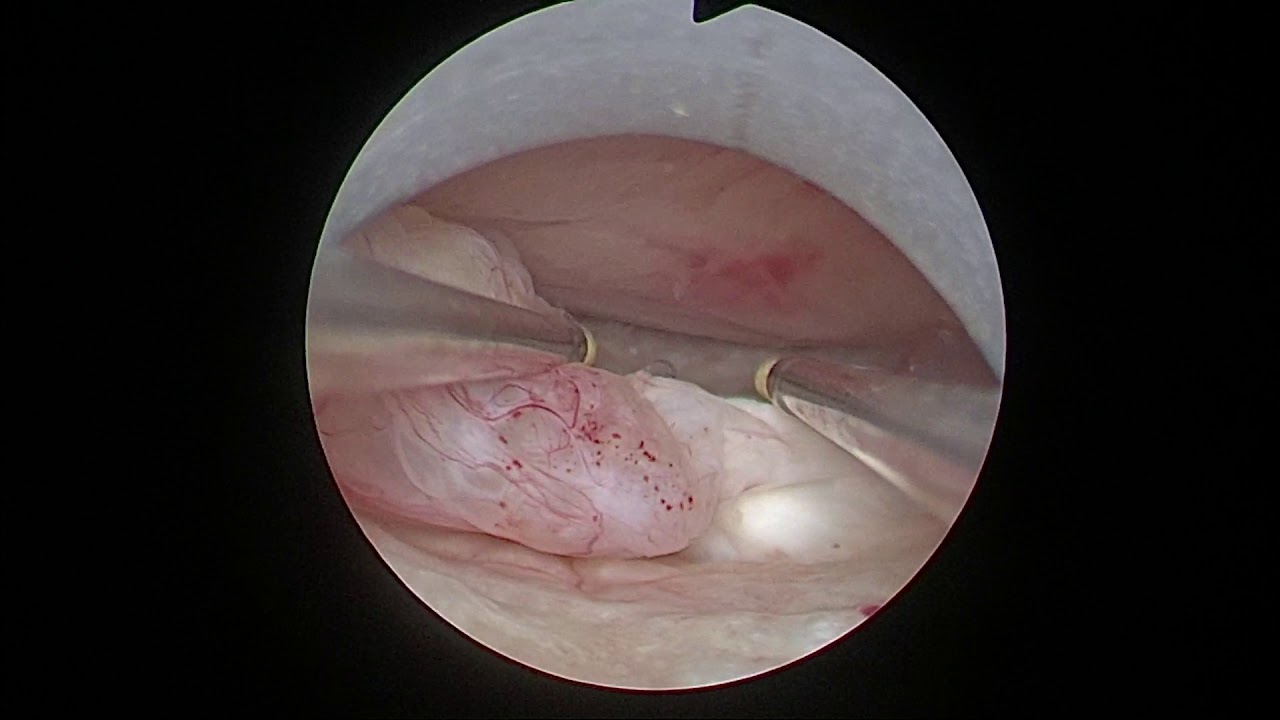

Sono Domenico Incandela, specialista in Ginecologia e Ostetricia e Fisiopatologia della Riproduzione. Sono Dirigente Medico I liv. con incarico di Alta specializzazione in diagnosi e cura dell'Endometriosi presso l'ARNAS Ospedale Civico di Palermo dove sono responsabile del Servizio di Isteroscopia e dell' Ambulatorio di Endometriosi presso il Centro di riferimento regionale per l'Endometriosi . Sin dall'inizio della mia attività mi sono occupato di gravidanza e diagnosi prenatale, negli anni ho curato la pratica e lo studio dell'endoscopia ginecologica (Laparoscopia e Isteroscopia) e della diagnosi e cura dell'Endometriosi . Presso il mio studio viene posta grande attenzione a ciò che concerne l'assistenza alla donna in gravidanza e successivamente in puerperio In tal senso è presente un Pelvic Center volto alla riabilitazione del pavimento pelvico attraverso l'ausilio di apparecchiature a radiofrequenza , sia in fase pre e post partum, in donne con atrofia vulvo-vaginale in menopausa o con condizioni di vulvodinia e dispareunia in genere, condizione molto frequente anche nella paziente affetta da endometriosi. Mi avvalgo inoltre dell'utilizzo dell'ozonoterapia strumento fondamentale per il trattamento di infezioni vagino\urinarie ricorrenti, infezioni virali quali l'HPV o condizioni di atrofia vulvo-vaginale menopausa correlate.

• Chirurgia endoscopica ginecologica

Per ciò che concerne la ginecologia mi occupo di diagnosi e cura dell'endometriosi, diagnosi e cura della patologia cervicale con l'esecuzione di colposcopia ,tamponi cervicali e buccali per HPV, trattamento di tutte le patologie uterine effettuando presso il mio studio isteroscopie office, consulenze contraccettive e per infertilità di coppia . Collabora con me una psicologa, la Dott.ssa Arianna Mellina, per il supporto alle problematiche di coppia di natura sessuale, il supporto alla paziente con vaginismo e vulvodinia, alla paziente con Endometriosi